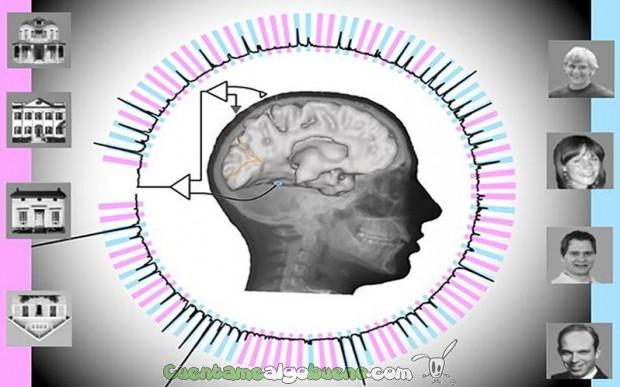

Aprovechando que debían pasar por quirófano de un modo u otro, el equipo les enroló para una prueba en la que las señales de los electrodos se conectaron a un potente software de cálculo. Durante la prueba, los sujetos iban viendo diferentes imágenes de caras y casas en rápida sucesión y debían identificar la imagen que estaba boca abajo.

Mientras tanto, el algoritmo se entrenaba para reconocer los patrones de estímulos que recibe ese área del cerebro al ver diferentes imágenes. Con el tiempo, ha logrado reconocer esas imágenes con un 96% de efectividad y prácticamente al mismo tiempo que lo hace el cerebro.